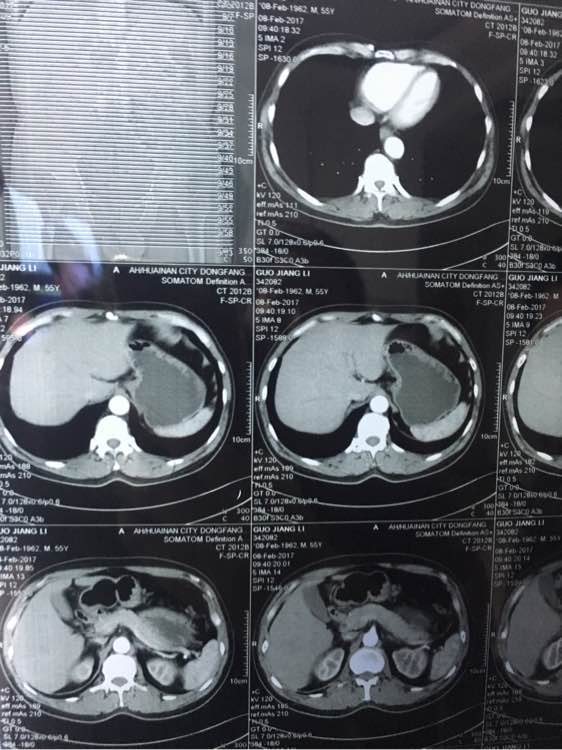

大神看下,几个月前说肠子

ct吧

几个月前说有点东西,肠子上

兄弟 你拍的有点多啊 全腹部ct?